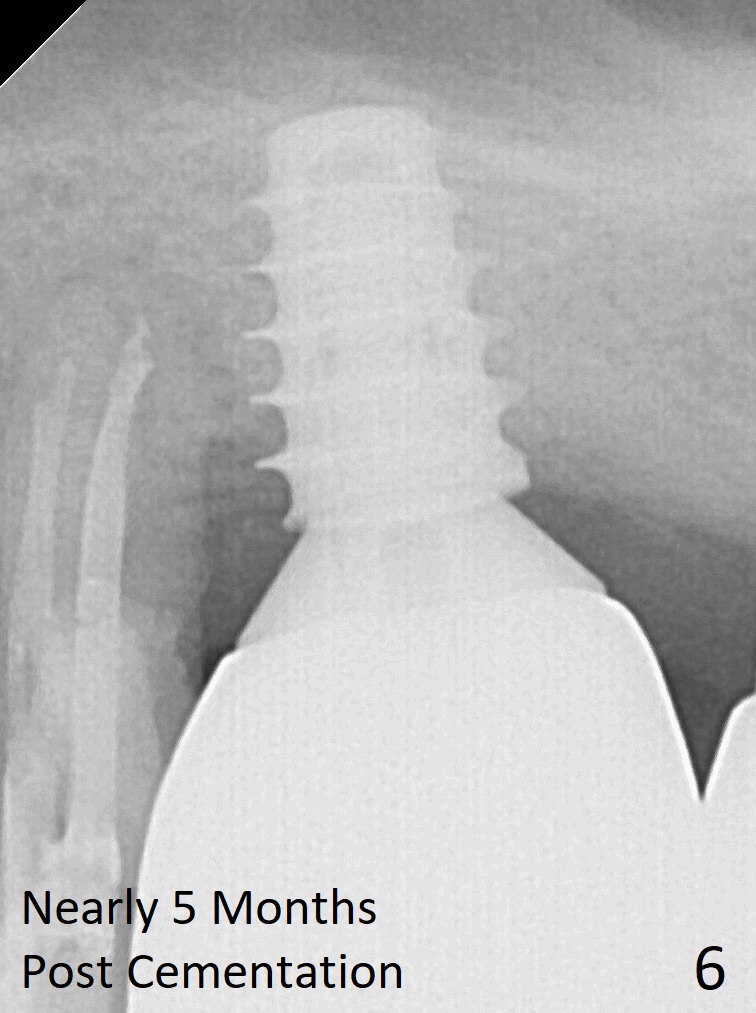

Four months post bone graft, the bone height at #14 is ~ 5 mm (Fig.1). After osteotomy for 4 mm with 4.3 mm Magic Drill (hard bone), Magic Sinus Lifter is used for sinus lift for ~ 8 mm without sinus membrane perforation. Perforation occurs with pulsating hemorrhage after sinus lift with allograft (.5-1 mm, mixed with Metronidazole). Collagen plug is used to repair the perforation before placing a short (5x7 mm) IBS implant with ~ 25 Ncm (Fig.2). After placing a 6.5x5.7(3) mm abutment, allograft is placed around the most coronal exposed implant thread (^). Acrylic is applied over the abutment for wound protection. There is mild nasal hemorrhage for 2 days postop. To prevent and treat sinus membrane perforation, PRF will be routine prepared preop for future cases. New bone forms apically and coronally 4.5 months postop (Fig.3,4 ^). A new temporary crown is fabricated so that it can undergo progressive loading for a few months before final impression. The definitive restoration is delivered 7.5 months postop (Fig.5). The bone density apical to the implant becomes apparently denser nearly 5 months post cementation (Fig.6). The bone density in the crest increases 2 years post cementation (Fig.7 *).